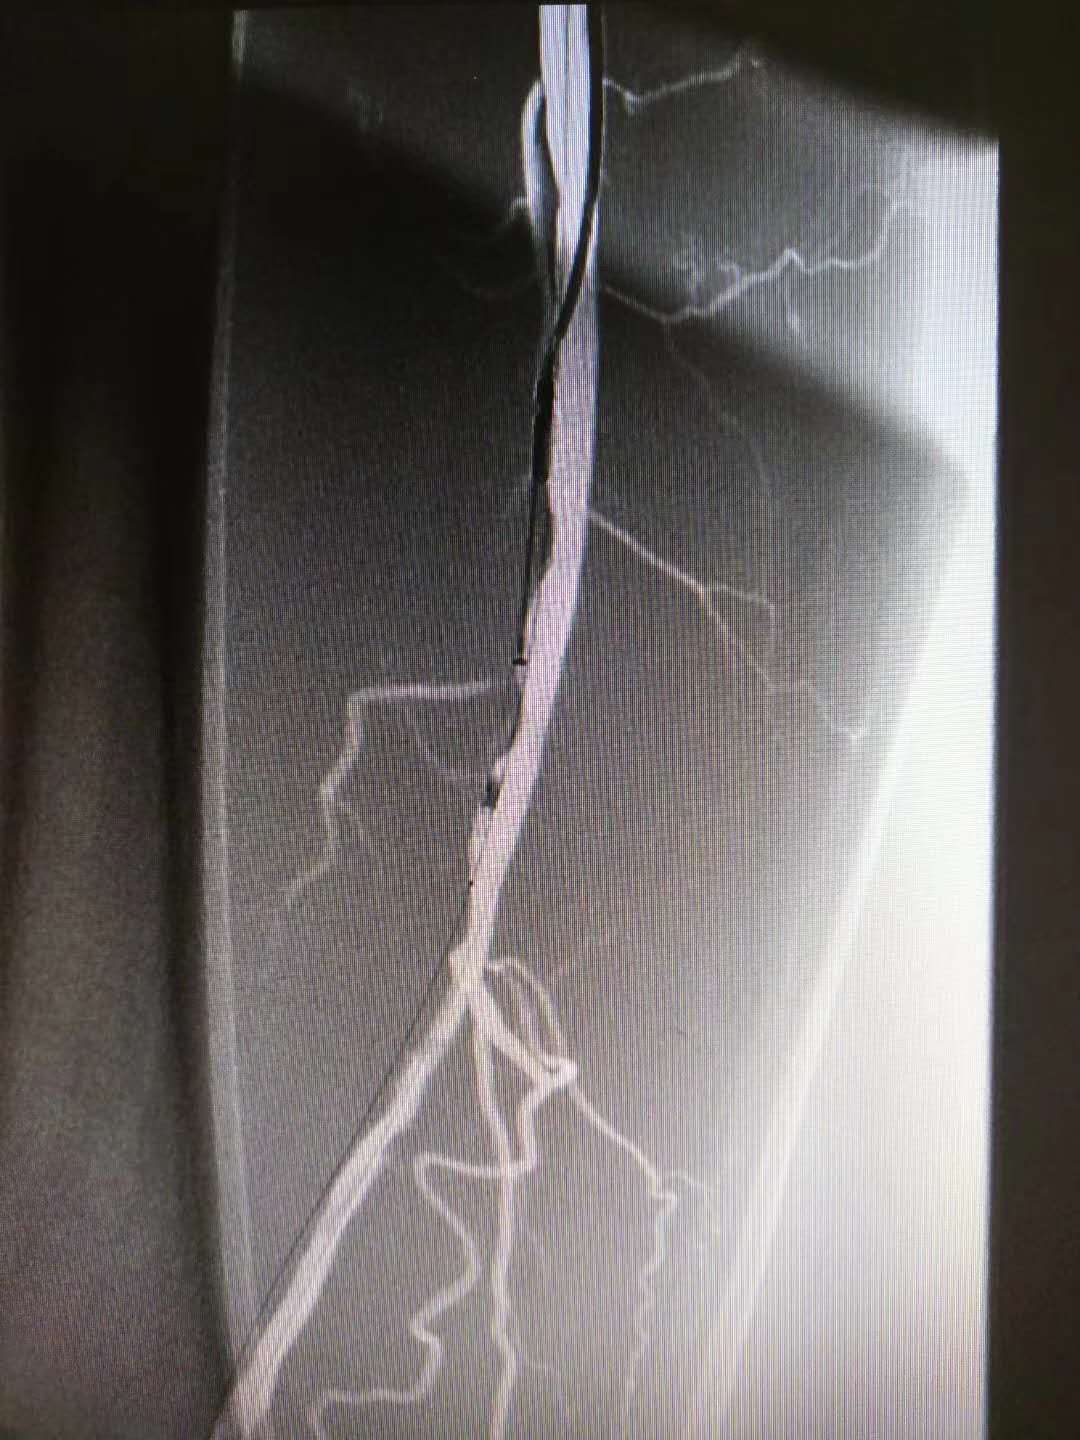

在成功开通闭塞性病变,将导丝送至远端,经过预先的球囊扩张准备后,使用动脉斑块旋切刀对病变部位行旋切,切除大量动脉硬化斑块。